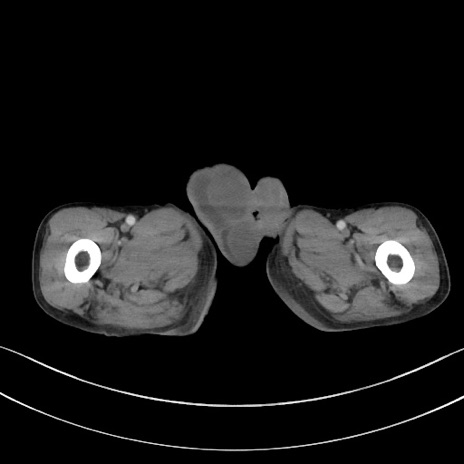

症例3(横断像)

症例

【症例】 70歳代男性

【主訴】右鼠径部腫瘤、疼痛

【現病歴】本日朝より上記主訴あり、受診。

【既往歴】膀胱癌にて膀胱全摘、両側尿管皮膚瘻

【データ】WBC 5600、CRP 0.56